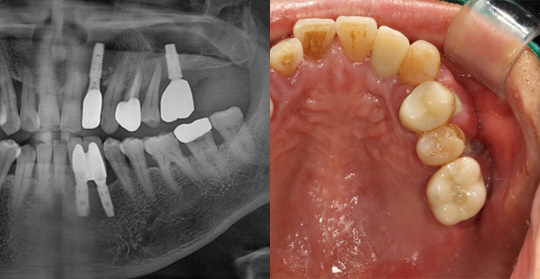

(61세 남 환자)